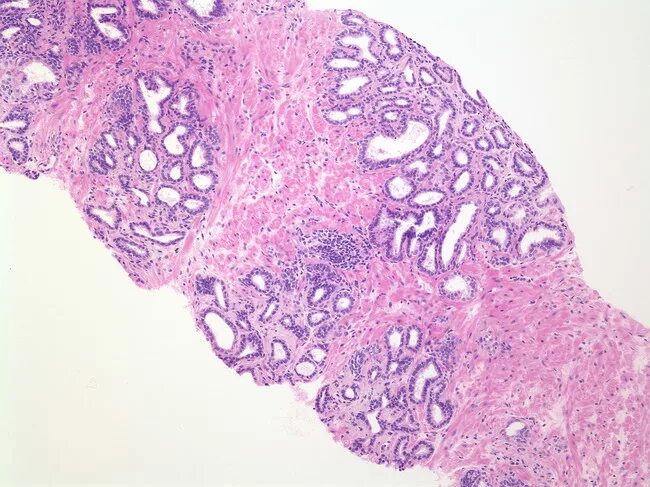

Гистология месяц